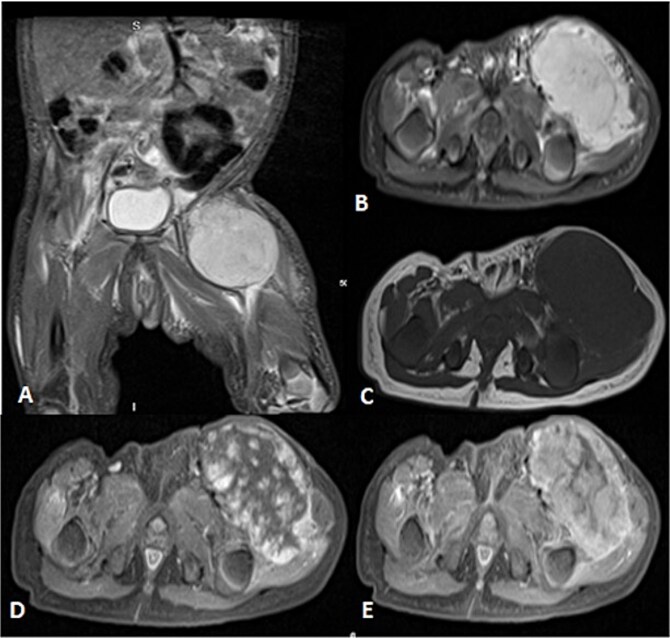

婴儿血管瘤(his)是最常见的婴儿肿瘤。它们是良性的,通常对心得安有反应。IHs很难与恶性软组织肿瘤如肉瘤区分。肉瘤是一种罕见的间充质肿瘤,类似于血管瘤,延迟治疗并影响预后。我们报告两例女婴的肉瘤最初被误诊为血管瘤。在第一个病例中,对1个月大的左腹股沟肿块患者使用丙泊洛尔。影像学显示为血管瘤。肿瘤生长需要活检,发现是肉瘤。在第二个病例中,一个2个月大的婴儿表现为快速增长和溃疡性左手肿胀,并被误诊为血管瘤。影像学和活检显示转移性肉瘤。两名患者都发生了脑转移并去世。这些病例强调,当遇到快速生长或溃疡时,需要重新评估his。早期发现对于获得最佳结果至关重要。

Infantile hemangiomas (IHs) are the most common infantile tumors. They are benign and often responsive to propranolol. IHs are difficult to distinguish from malignant soft tissue tumors like sarcomas. Sarcomas are rare mesenchymal tumors that mimic hemangiomas, delaying treatment and affecting outcomes. We report two instances in which female infants with sarcomas were initially misdiagnosed as hemangiomas. In the first case, propanolol was administered to a 1-month-old presenting with a left inguinal mass. Imaging revealed a hemangioma. Tumor growth necessitated a biopsy, revealing a sarcoma. In the second case, a 2-month-old presented with a rapid growing and ulcerating left-hand swelling and was misdiagnosed as a hemangioma. Imaging and biopsy revealed metastatic sarcoma. Both patients developed brain metastases and passed away. These cases highlight that IHs need to be re-evaluated when rapid growth or ulceration is encountered. Early detection is essential for optimal outcomes.